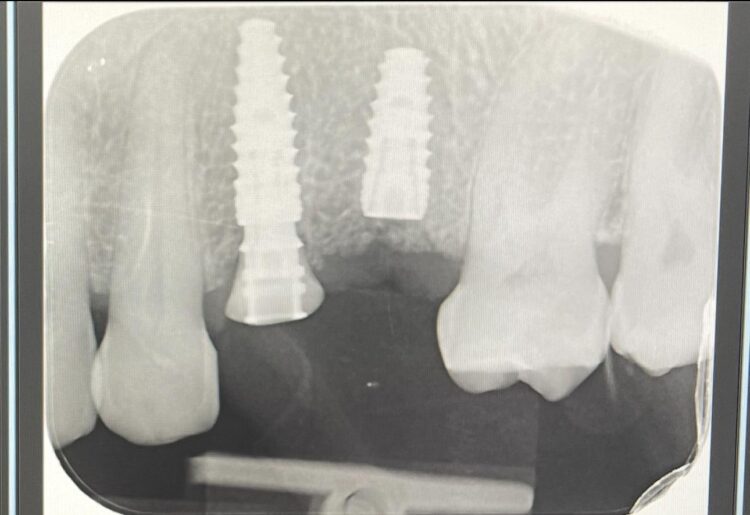

Approximately 15mm of space was available between the distal of the UR3 and mesial of the UR6, which highlighted the importance of absolute accuracy when positioning the implants. Guided surgery was, therefore, indicated as a way of optimising precision.

Two 3.8mm diameter CONELOG® Progressive-Line implants were placed through the guide, following the plan precisely. The UL4 implant was longer (11mm) to ensure sufficient apical bone was engaged for primary stability, it was also positioned in the palatal root to ensure good engagement with the bone and better bone to implant contact. A sizable jump gap was noted between the implant and the buccal plate of around 5-6mm. From a biological perspective, the jump gap can be left because the ridge would heal to leave a sufficient buccal plate. However, the literature[iv] shows that grafting reduces the amount of bone resorption post implant placement, which was one of the reasons that augmentation was indicated in this case.

Another predetermined concern was the amount of remaining bone surrounding an implant after placement. There was less than 2mm of residual bone buccal to the UL5 site once the implant was placed. Alberto Monje et al. (2023) [v] showed that thin buccal bone at the implant site increases the risk of major dimensional changes, this can have direct implications on the aesthetics and functional outcomes.

An x-ray was taken immediately post-operatively to confirm that the temporary cylinder was seated correctly and wasn’t catching on the socket walls. This image also provided a reference for the custom healing abutment position and ensured that the bone graft material added to the jump gaps wasn’t preventing this abutment from fully seating.